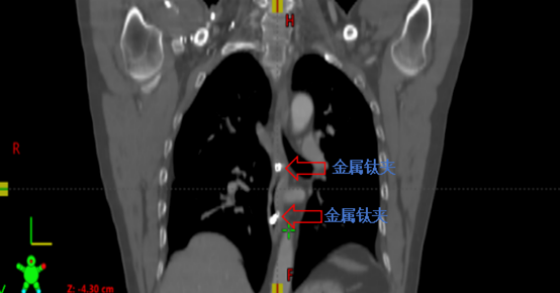

金属钛夹标记病变部位 肿瘤靶区范围 家住常德安乡县的高先生在2019年不幸罹患下咽-颈段食管癌,在湘雅常德医院肿瘤科进行了同步放化疗之后病情得到康复。近日,高先生突然胸...